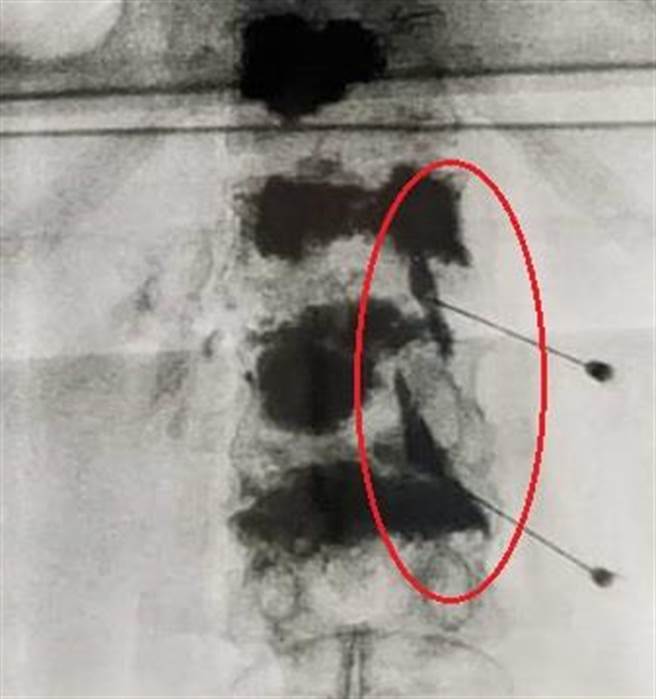

60岁苏先生1年多前曾因胸、腰椎压迫性骨折开刀,近日下背疼痛加剧,透过在背部脊椎神经根周围注射类固醇及局部麻醉药,疼痛大幅减缓。(大里仁爱医院提供/潘虹恩台中传真)

60岁苏先生1年多前曾因胸、腰椎压迫性骨折开刀,近日下背疼痛加剧,严重影响生活品质,与大里仁爱医院神经外科医师贾开杰讨论后,接受神经阻断术,透过在背部脊椎神经根周围注射类固醇及局部麻醉药,减缓疼痛,后续再至门诊追踪,苏先生背痛大幅缓解。

贾开杰指出,神经阻断术具有诊断及治疗的功能,可以大幅缓解因创伤或是脊椎手术后产生短期且剧烈的急性疼痛。药剂施打过程约20至30分钟,止痛效果虽因人而异,但通常能维持长达1个月。目前可由健保给付,自费部分则依病人是否额外增打PRP或羊膜到神经决定。